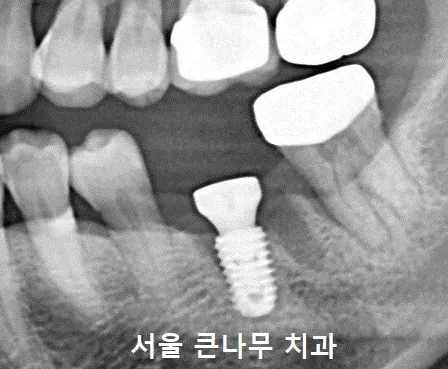

발치한 자리에는 임플란트를 식립하였고 시술을 마쳤습니다

이렇게 치아 뿌리가 파절된 케이스를 살펴보았는데요. 이가 없어도 임플란트 식립으로 기능을 회복할 수 있기 때문에 큰 문제는 없지만 평소 좋지 않은 생활습관에 따라 치아에 금이 가게 되는 경우가 있습니다.